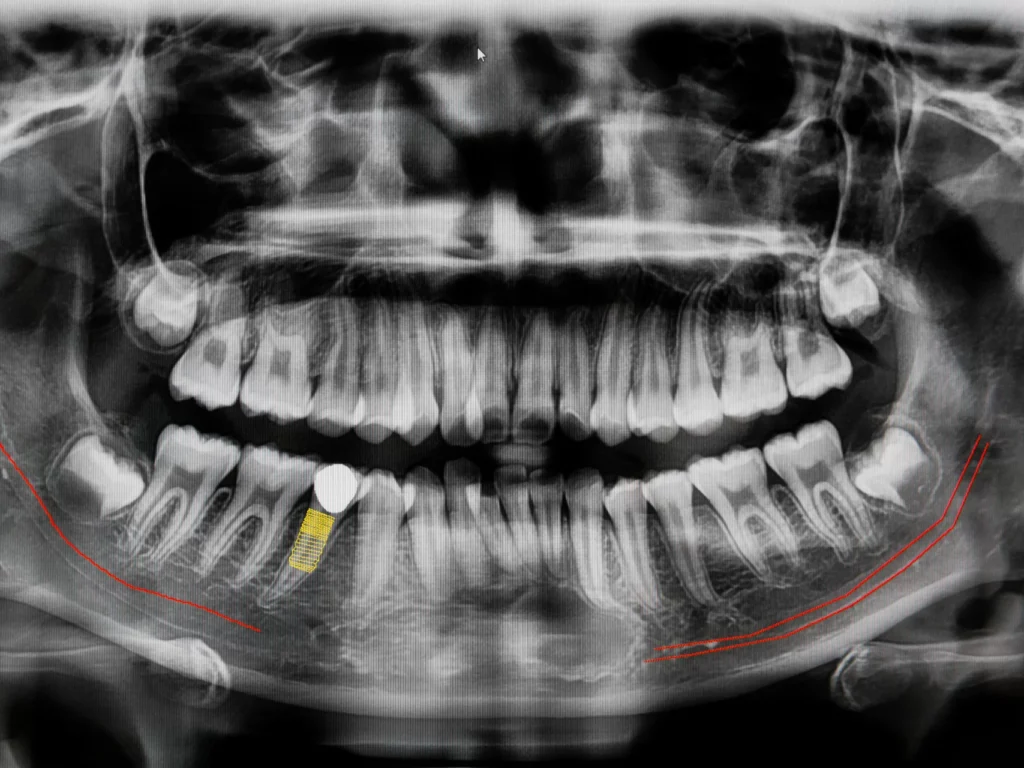

3D Imaging (CBCT)

CBCT stands for ConeBeam Computed Tomography, which is a special type of digital x-ray scanner that dentists use to see a 3D image of your mouth and teeth.

The ConeBeam CT imaging system rotates once around your head while you stand or sit in a chair. The process is quick, simple, and completely painless. We use these scans to provide the best treatment in dental implants, root canals, diagnosis of dental and facial pain, etc.

We can evaluate your teeth and facial structures from literally every angle, in 3D, and in color! Routine x-rays, on the other hand, produce a single flat image with limited information.

You can have absolute confidence and satisfaction in the treatment you receive, knowing we've analyzed every problem with 3D technology.